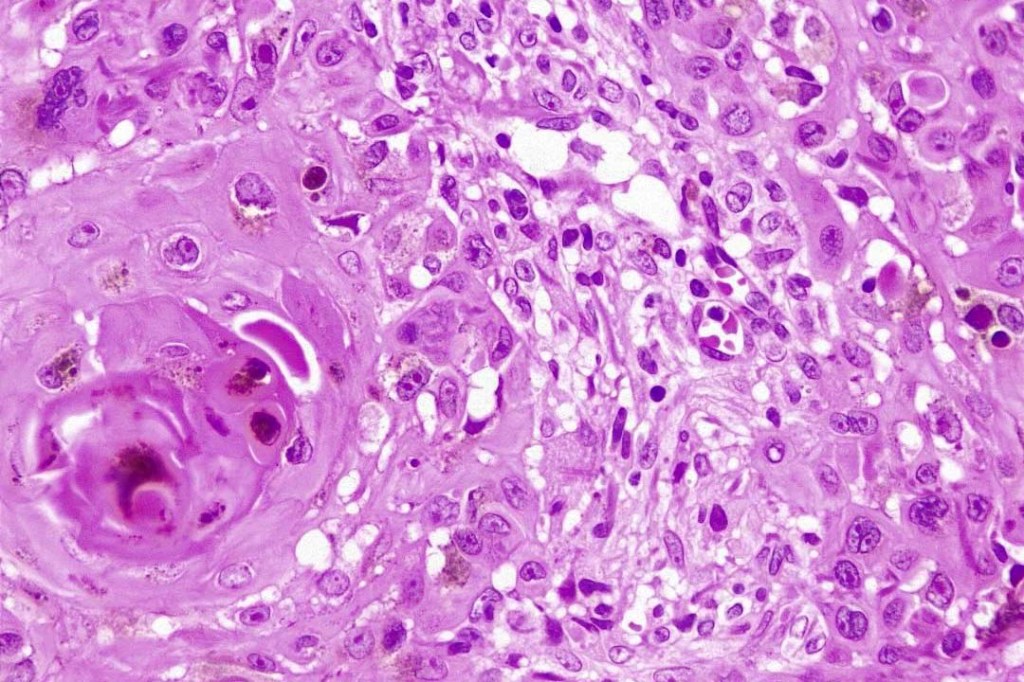

An exceedingly rare collision tumor composed of an admixture of squamous cell carcinoma/basal cell carcinoma/trichoblastoma respectively and melanoma. Although most appear to have behaved in a benign fashion, a malignant basomelanocytic tumor is illustrated below. More cases will be need to be stidies/published before the true biological behavior of this group of tumors can be satisfactorily elucidated. I think that complete excision should be the rule and a careful follow-up recomended.

Basomelanocytic tumor

Squamomelanocytic tumor